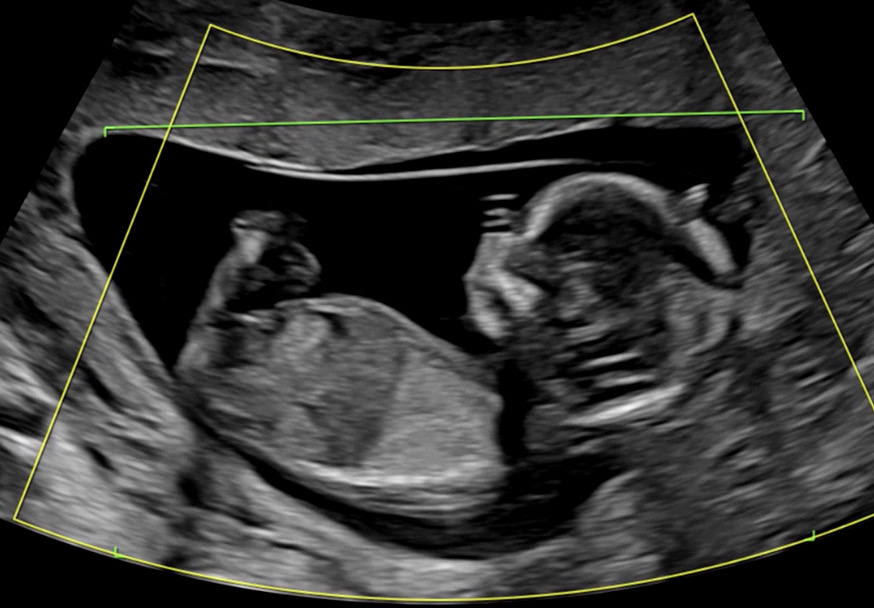

12주차 6일 각도법 잘보시는분 계시나용??

진짜 성별이 너무너무 궁금한데 각도법으로 예측할수 있다고 하더라구요! 각도법 잘 보시는분 계신가요?? 한번만 봐주세요!ㅎㅎㅎ

갈라져있는 거 보니까 딸같아요